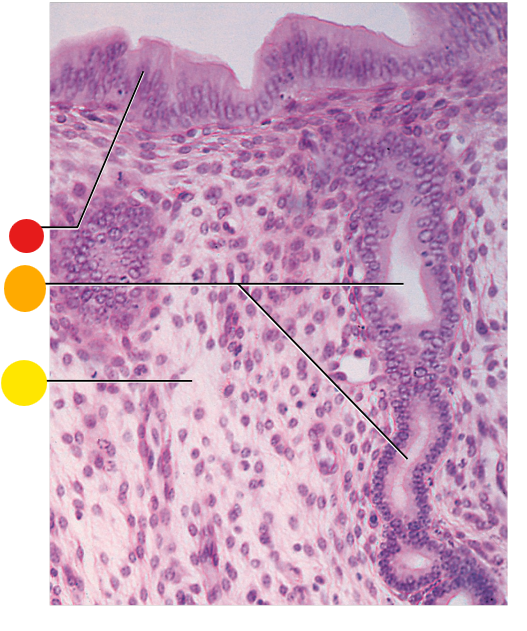

red

granulosa cells

orange

thecal cells

yellow

zona pellucida

What is this

secondary follicle